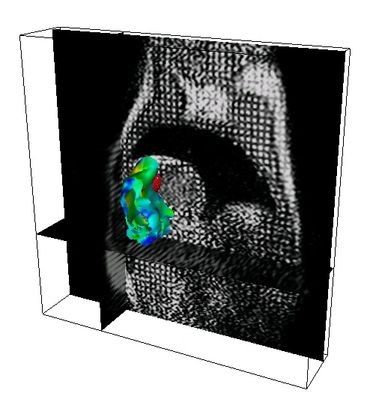

DescargarIntervención: Electro-Fisio XMR Ablación (FMIH05) (pdf)

DescargarLocalization of Abnormal Electric Pathways (MICCAI05) (pdf)

TODOS LOS CÁLCULOS, IMÁGENES Y ANIMACIONES en esta página y artículos, fueron producidos con PROGRAMAS ESCRITOS POR MI en C / C++ y VTK/TCL/TK